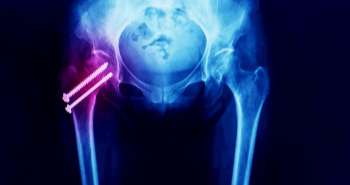

Ultrasound-Guided Calcium Debridement of shoulder joint delay the requirement for further invasive treatments in patients with calcium deposits in shoulder.

According to a recently published research in the Journal Surgical Technology International, ultrasound-guided calcium debridement is an effective, safe and satisfactory approach for treatment of calcium deposits in shoulder. The study involved the assessment of pain, patient’s satisfaction, function, activity levels and associated complications of patients who went through this procedure from 2005 to 2015.